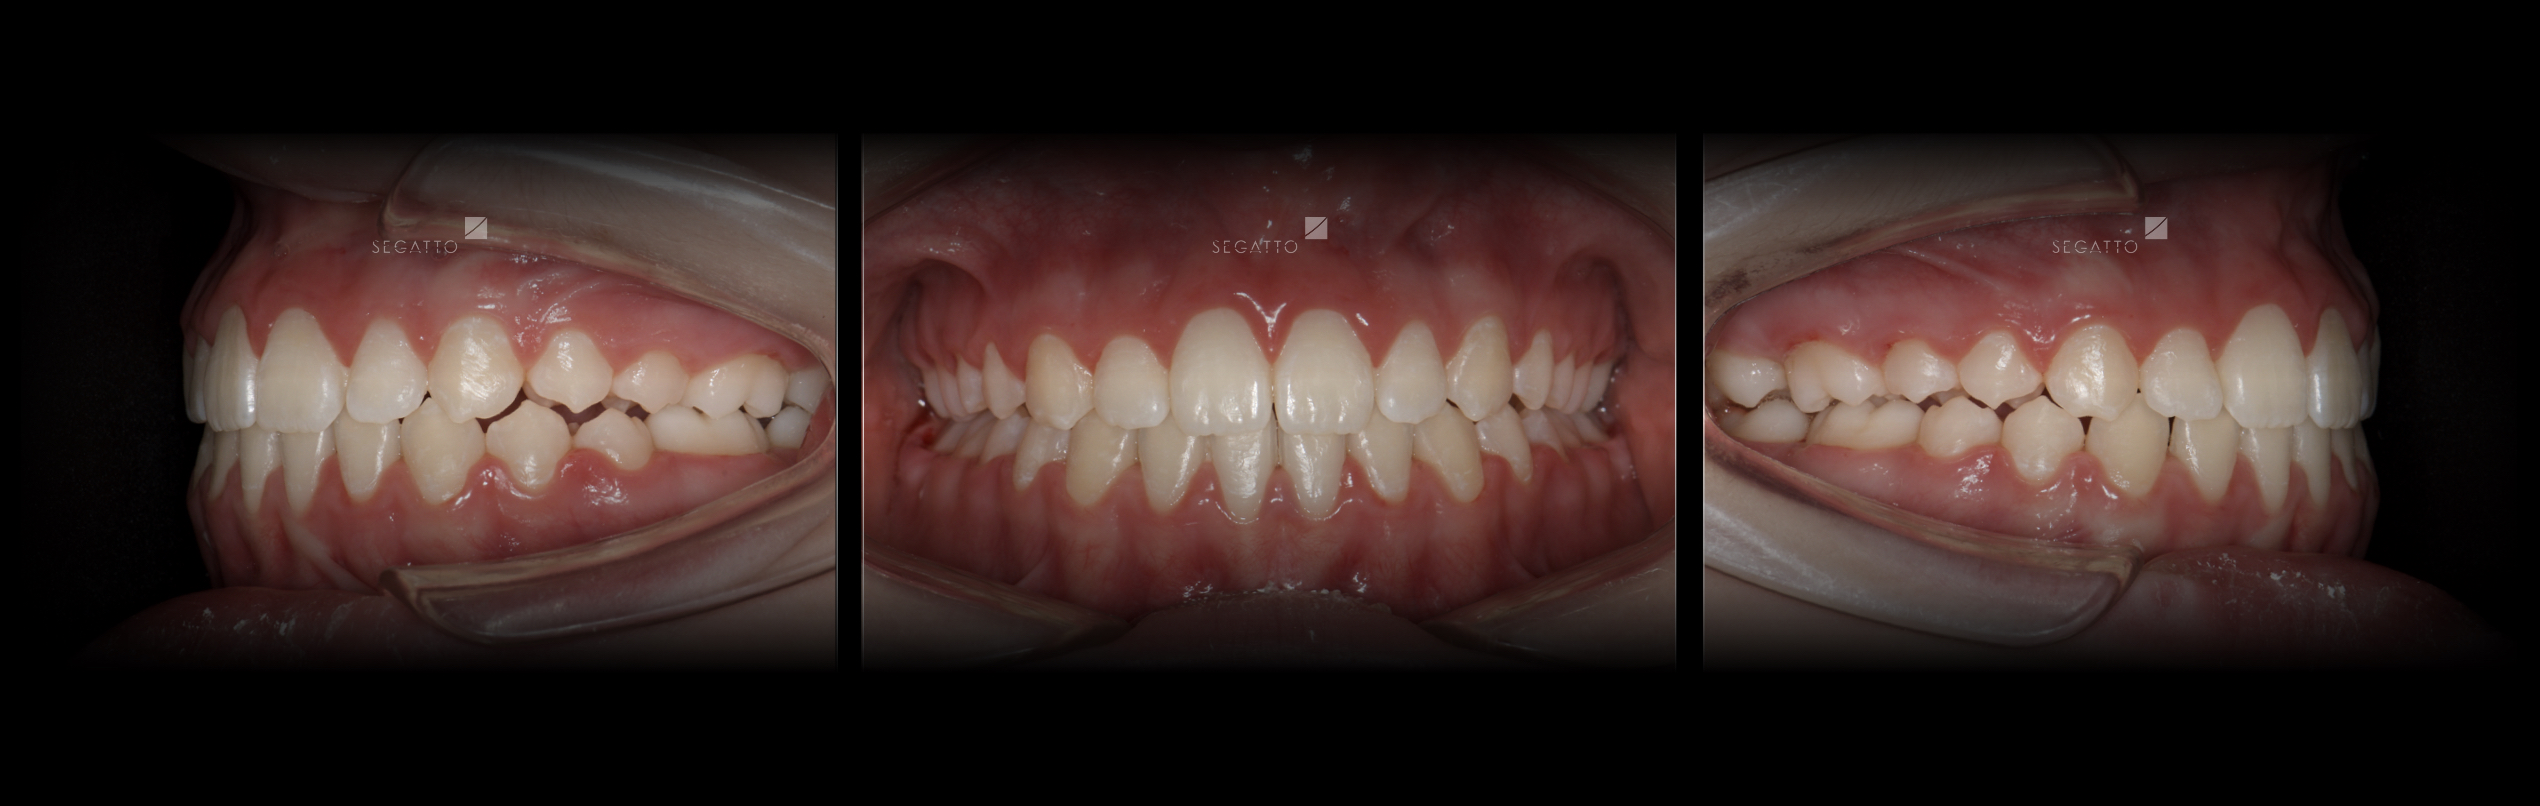

Orthodontics

Cases